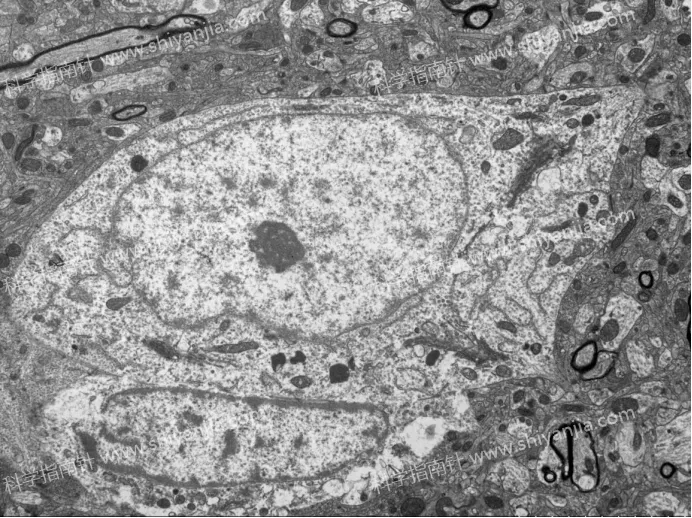

3.5 分钟是损伤临界值:无论是否灌流,取材时间超过 5 分钟,样本都会出现明显的缺氧损伤,空泡形成、线粒体肿胀等问题频发,实验可重复性大幅降低。

灌流组

4.不同结构耐受度不同:髓鞘和突触对短时间缺血具有相对耐受性,受灌注处理和短时间取材延迟的影响较小。